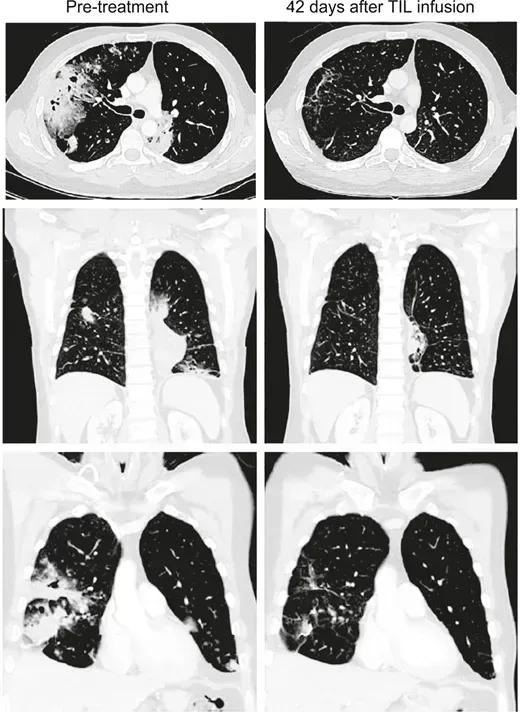

患者2是一位67岁女性,因肿瘤破裂出血接受经肝动脉栓塞术后1周入院。CT显示肝左叶147×79mm混合信号肿块,双肺存在多个散在结节,右肺中叶最大结节直径18mm。甲胎蛋白水平14,529ng/mL,确诊为HBV相关性肝细胞癌,BCLC分期为C期。

该患者入组后,接受了姑息性左半肝切除术,在TIL培养29天后,先后接受淋巴细胞清除治疗+自体TIL细胞单次输注+IL-2治疗+特瑞普利单抗治疗(18个疗程)。

结果显示:肝切除术后1个月,肺转移灶进展,右肺结节增大至25mm;接受TIL输注及常规抗PD-1治疗后,术后10个月肺病灶完全消失,至今24个月仍保持无瘤状态(详见下图c、d)。

▲图源“Liver Cancer”,版权归原作者所有,如无意中侵犯了知识产权,请联系我们删除